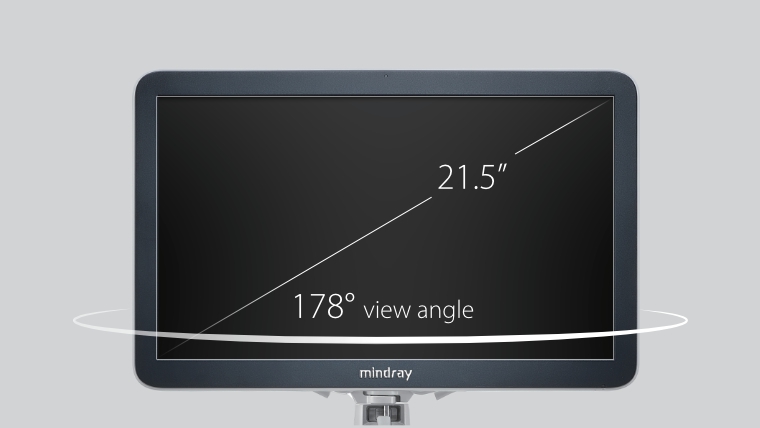

eXceeding Experience

Experiencia con alta productividad